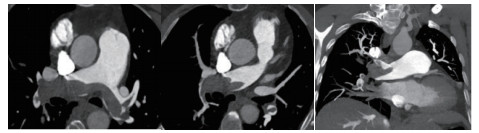

例2 72岁,男性。主因“活动后气短3 d,加重伴有晕厥1次”住院。既往体健,否认制动史及手术史。入院查体:神志清楚,体温36℃,血压120/70 mmHg,脉搏110次/min,呼吸22次/min,脉氧93%(安静,空气氧),轻度乏氧征。双肺呼吸音清,未闻及干湿性啰音。心率110次/min,心律齐,P2 > A2,心界无扩大,无杂音。腹软,无压痛,肠鸣音正常,双下肢无浮肿。神经系统查体未见异常。血气分析(安静,空气氧)提示pH 7.457,PaCO2 26.7 mmHg,PaO2 74.0 mmHg,SaO2 95.5%;D-Dimer 13 743 ng/ml;FDP 175.060 μg/mL,FBG 1.990 g/L;PLT:224 G/L;cTnI 0.04 ng/mL,BNP 666 pg /mL;ALT 15 U/L,AST 27 U/L,CREA 103.3 mmol/L,血Na+、K+、Cl-:正常范围;UCG提示:右心增大,肺动脉主干增宽(28 mm),三尖瓣反流(中-重度),反流面积11.5 cm2,TI法估计SPAP为50 mmHg、左室舒末内径38 mm、左心功能稍减低E波/A波= 60/40 cm/s,未见节段性室壁运动障碍;双下肢静脉超声提示右侧股总、股深、股浅、腘静脉及双侧小腿肌间静脉丛血栓形成。心电图(图 5所示)提示窦性心动过速;CTPA提示双肺主干明确充盈缺损(图 6所示)。入院诊断:急性PE(中高危)。给予低分子肝素重叠华法令抗凝治疗。D-Dimer由入院时13 743 ng/mL分别降至第2天10 000 ng/mL,第3天9 000 ng/mL和第四天的5 000 ng/mL。住院第4天开始出现纳差、恶心未吐,复查心电图提示窦性心动过速,SⅠQⅢTⅢ,胸导T波加深(如图 7所示)。入院第5天床上排便后出现呼吸急促,储氧面罩吸氧(Flow 10 L/min)维持氧合78%(当天INR 2.02),15 min后出现血压、心率下降至消失,心外按压始终无自主呼吸及心律恢复,因家属放弃系统溶栓治疗,抢救2 h无效宣告患者临床死亡。回顾入院后连续复查的心电图提示右心负荷有逐渐加重及胸前导联缺血加重的倾向;UCG同样证实右心室内径呈进行性增大的趋势(分别为入院时的右心房31 mm×47 mm、第2天28 mm×40 mm和第4天的54 mm×60 mm)。

| 图 6 入院时CTPA提示双肺主干明确充盈缺损 |

| 图 7 入院第4天病情变化时心电图变化。窦性心动过速,SⅠQⅢTⅢ,胸前导联T波加深 |